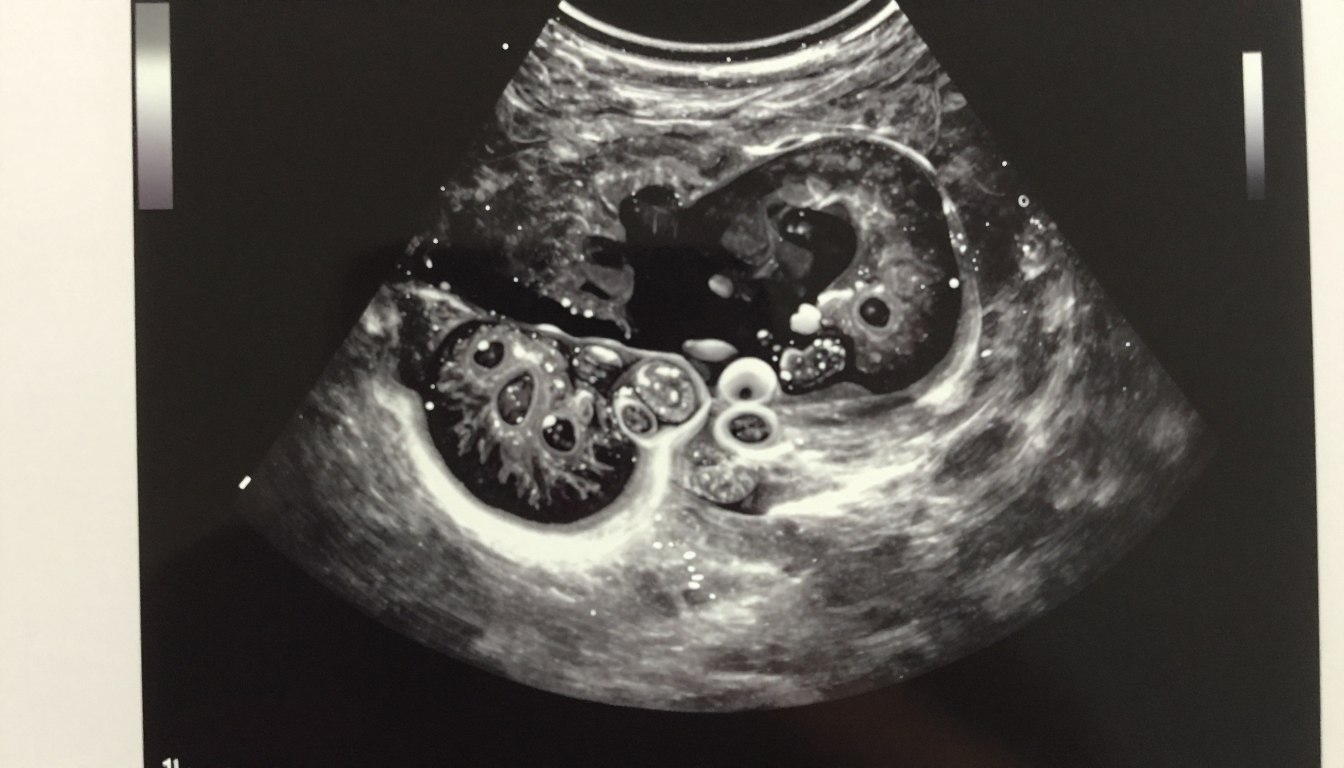

Dowiedz się więcejZdjęcia USG – jak odczytywać obraz i co warto zachować z badania

Czy wiesz, dlaczego na wydruku widzisz „plamy”, a lekarz odczytuje konkretne struktury? To pytanie otwiera nasz krótki poradnik. W…